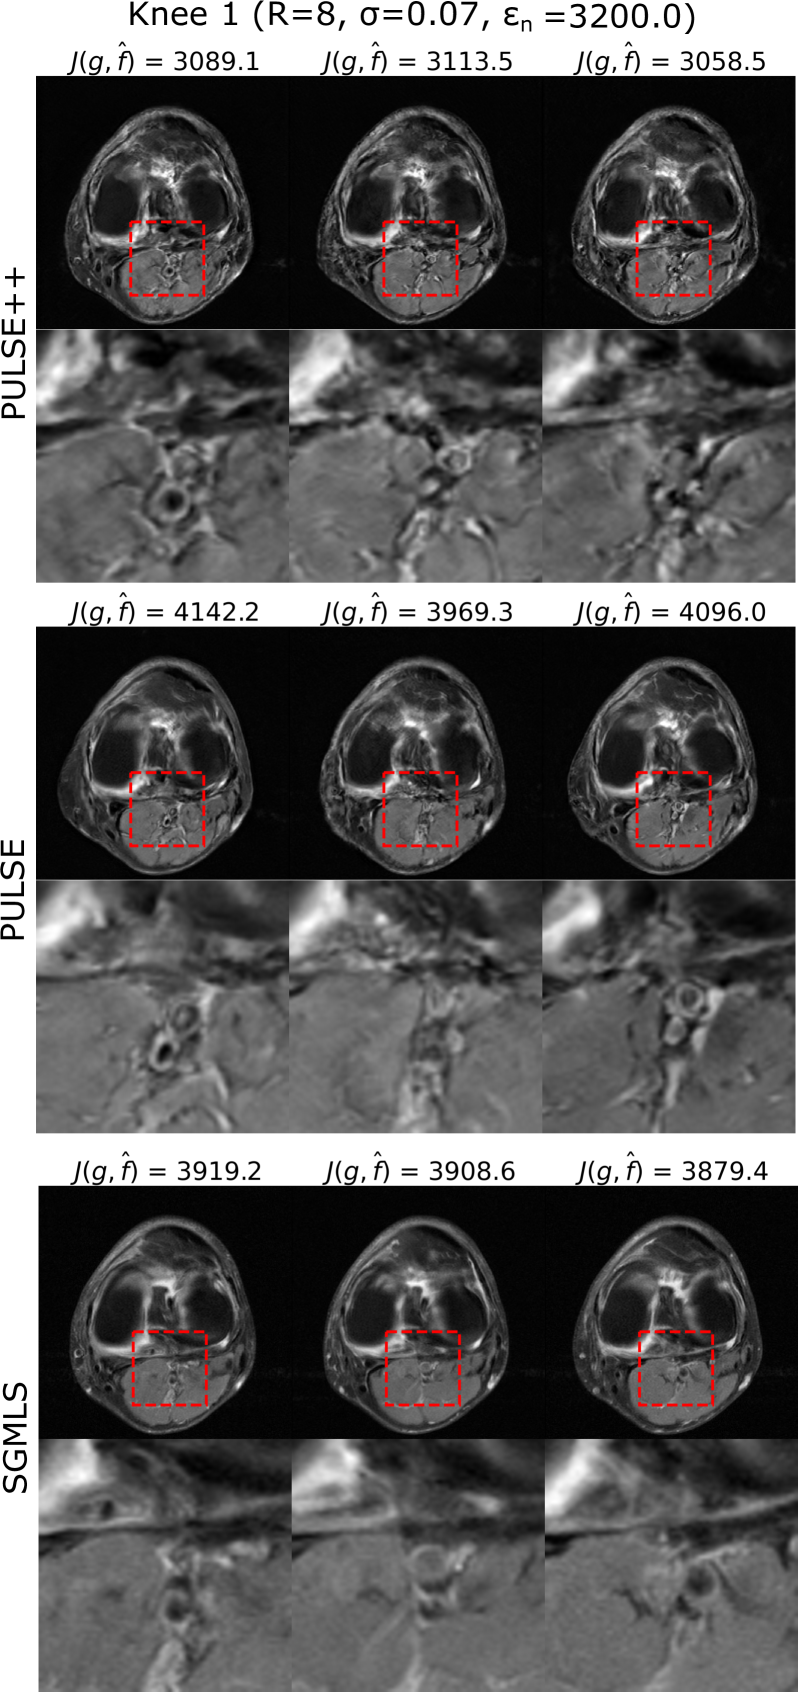

Samples of alternate solutions generated by PULSE++ (γ=0.001,λc=0.01formulae-sequence𝛾0.001subscript𝜆𝑐0.01\gamma=0.001,\lambda_{c}=0.01), PULSE (λg=0.1subscript𝜆𝑔0.1\lambda_{g}=0.1) and SGMLS (η=2×107𝜂2superscript107\eta=2\times 10^{-7}) from the same k-space data produced by Knee 1, corresponding to R=8𝑅8R=8 and σ=0.07𝜎0.07\sigma=0.07, are shown in Fig. 4. For each method, the alternate solutions exhibit considerable diversity while being produced by use of the same measurement data. Additional examples of alternate solutions obtained with the PULSE++, PULSE and SGMLS methods are provided in the form of supplementary material as described in the Appendix. However, among the three methods, only the alternate solutions produced by the PULSE++ method satisfied the stipulated data-consistency criterion based on Morozov’s discrepancy principle. This establishes an advantage of the PULSE++ method over PULSE in achieving the desired data consistency by properly accounting for the heavy tails of the empirical distribution of the latent style vectors in 𝒱+superscript𝒱\mathcal{V}^{+}. This also demonstrates the superiority of PULSE++ over SGMLS in preserving data consistency of alternate solutions.

Refer to caption

Figure 4: Samples of alternate solutions 𝐟^^𝐟\hat{\mathbf{f}} obtained using PULSE++, PULSE and score-based posterior sampling from the same k-space data 𝐠𝐠\mathbf{g} produced from Knee 1 for R=8𝑅8R=8 and σ=0.07𝜎0.07\sigma=0.07, with the data consistency tolerance ϵ𝐧=3200.0subscriptitalic-ϵ𝐧3200.0\epsilon_{\mathbf{n}}=3200.0. The data fidelity value 𝒥(𝐠,𝐟^)𝒥𝐠^𝐟\mathcal{J}(\mathbf{g},\hat{\mathbf{f}}) for each alternate solution 𝐟^^𝐟\hat{\mathbf{f}} is provided in the respective figure headings. Zoomed-in images of the same region indicated by a red bounding box are shown below each alternate solution that demonstrate distinct structures. However, only the alternate solutions produced by PULSE++ have data fidelity values lower than ϵ𝐧subscriptitalic-ϵ𝐧\epsilon_{\mathbf{n}}, while the alternate solutions obtained using PULSE and score-based posterior sampling are not data-consistent. All the alternate solutions are displayed in the grayscale range [0,1]01[0,1].